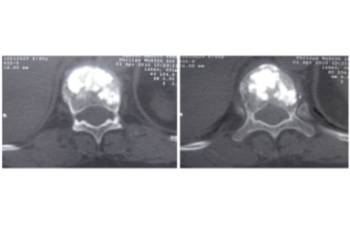

Clinical case example of a lumbar vertebral body resection (corpectomy) and reconstruction of a burst fracture at level L4.

Vertebral body resection (corpectomy) and reconstruction of complex vertebral and burst fractures

Severe vertebral body fractures, i.e. conminute and burst fractures, may require a partial vertebral body resection (corpectomy) and reconstruction with an expandable vertebral body cage. Especially severe fracture cases are also those with a bone fragment moving into the spinal canal that compresses on neural structures, such as the spinal cord and causes spinal canal stenosis. Corpectomy allows to resect most of the fractured body, including the bone fragments pushing on the nerves and intruding into the spinal canal. The vertebral body reconstruction is usually rounded up with a posterior augmented instrumented fusion of the adjacent levels to the fracture. All of this allows a proper healing of the fracture and the patient to recover without pain.